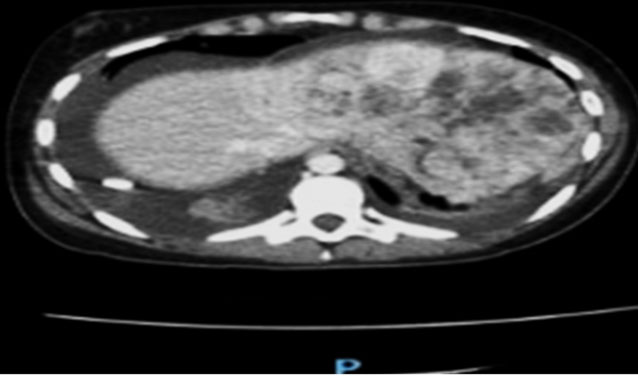

Case Report: The following outlines the case of a 2-year-old male who presented with a bump and swelling on the left side of his head. Imaging tests identified multiple, hyperdense, and focally ring-enhancing intra-axial lesions located mainly at the gray-white matter junction of bilateral frontal left-sided parietal, left-sided occipital, and left-sided temporal lobes. In addition, multiple lytic lesions were seen in the calvarium. Pathology confirmed EH. While one lesion required surgical resection, the remaining lesions showed spontaneous regression during follow-up.